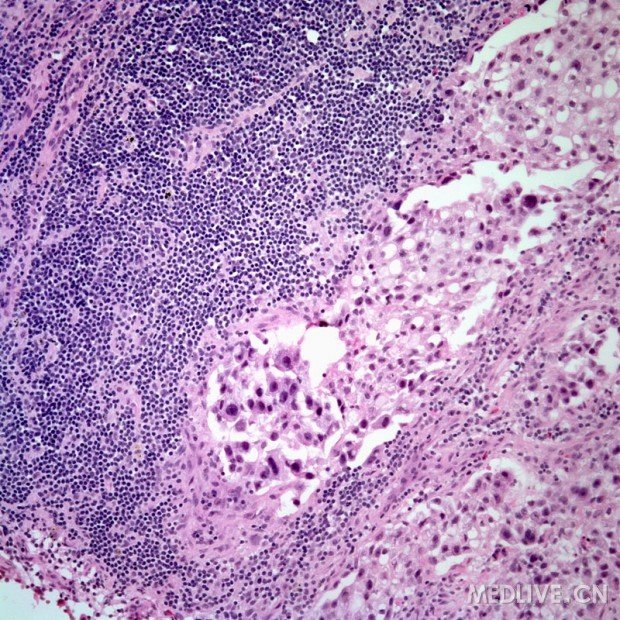

淋巴结活检镜下如图所示,应考虑何种疾病 ( ) -病理学高级职称题库总题库